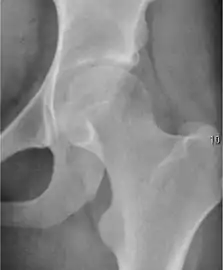

Osteoarthritis

In adults, one of the main indications for radiographs is the detection of osteoarthritic changes (Figure 1(e)). Nevertheless, radiographs usually detect advanced osteoarthritis that can be graded according to the Tönnis classifications. The grading system ranges from 0 to 3, where 0 shows no sign of osteoarthritis. Intermediate grade 1 shows mild sclerosis of the head and acetabulum, slight joint space narrowing, and marginal osteophyte lipping. Grade 2 presents with small cysts in the femoral head or acetabulum, moderate joint space narrowing, and moderate loss of sphericity of the femoral head. Grade 3 is the severest form of osteoarthritis, which manifests as severe narrowing of the joint space, large subchondral cyst with productive bone changes that may lead to deformity of the bone components of the joint, while secondary osteoarthritis due to calcium pyrophosphate deposition can be diagnosed when calcification of hyaline cartilage and fibrocartilage is detected.[1]